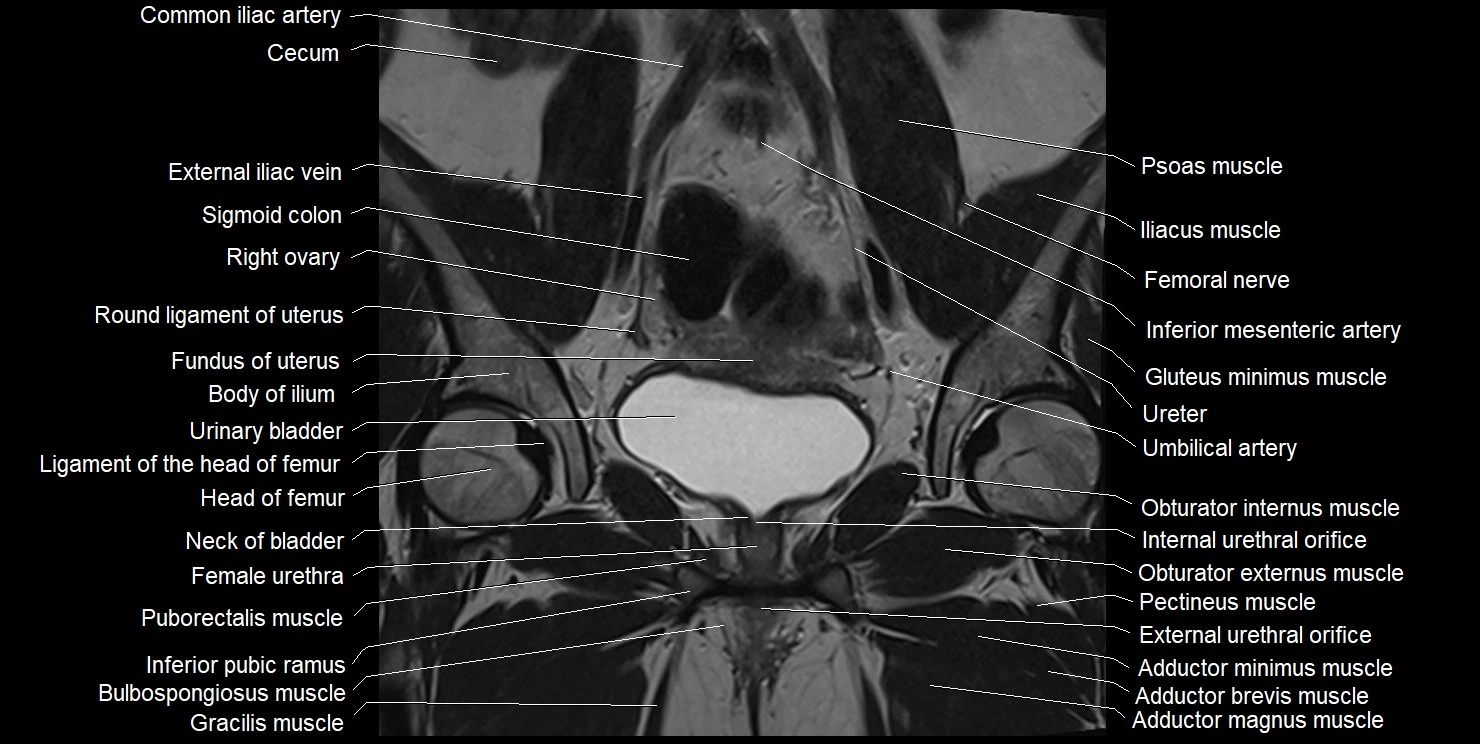

- Adductor brevis muscle

- Adductor magnus muscle

- Adductor minimus muscle

- Bulbospongiosus muscle (Female)

- Female urethra

- Gracilis muscle

- Head of femur

- Inferior pubic ramus

- Internal urethral orifice

- Neck of urinary bladder

- Obturator externus muscle

- Obturator internus muscle

- Pectineus muscle

- Puborectalis muscle

- Right ovary

- Urinary bladder